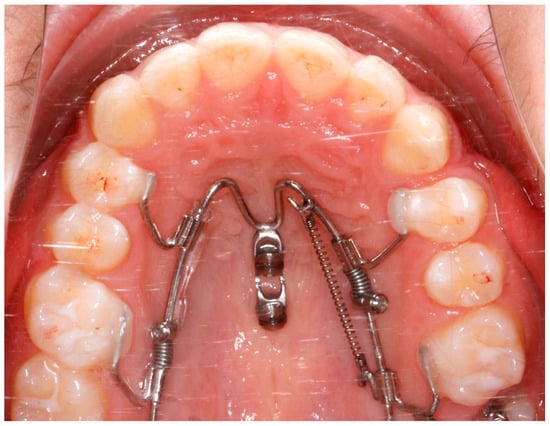

2.1. The Appliance

2.3. Case Description